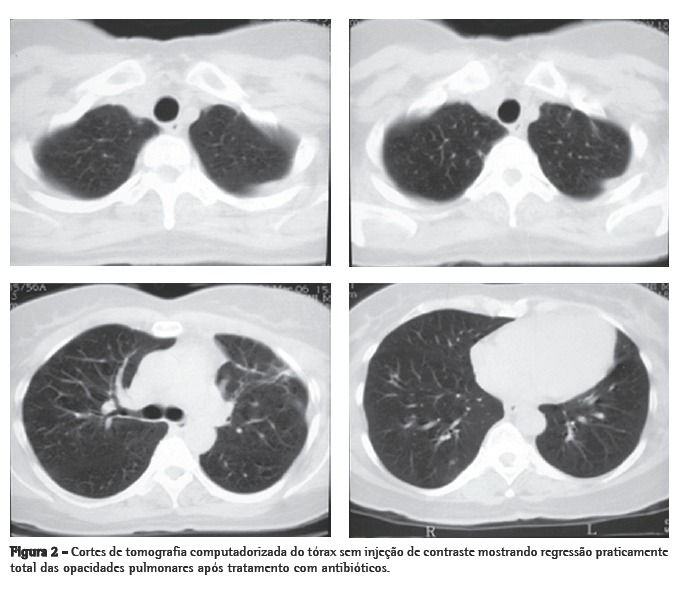

Mulher de 56 anos, branca, procurou o serviço de emergência devido à tumoração em região cervical à direita, dolorosa, há 5 dias. Apresentava tosse seca e febre alta há 3 dias. Negava tabagismo. Era hipertensa e diabética e havia tido um infarto do miocárdio há 3 anos. Na admissão, a paciente apresentava-se desidratada, afebril (temperatura axilar, 36,7°C), eupnéica, com tumoração cervical dolorosa à direita. Os exames laboratoriais revelaram velocidade de hemossedimentação aumentada (92 mm). A ecografia cervical mostrou trombose em VJI direita, sendo iniciada anticoagulação no quarto dia de internação. A radiografia de tórax demonstrou pelo menos dois nódulos no pulmão esquerdo, um aparentemente escavado e outro com 18 mm de diâmetro na base, além de lesão irregular com 25 mm de diâmetro no lobo superior direito. Foi realizado ecocardiograma transesofágico para descartar a hipótese de endocardite, o qual não demonstrou presença de vegetações. Devido à hipótese de pneumonia, foi iniciado tratamento empírico com 500 mg de cefuroxima, via oral, a cada 12 h. A tomografia de tórax revelou múltiplas opacidades bilaterais, de aspecto sugestivo de implante metastático (Figura 1). Prosseguindo a investigação, a paciente foi submetida à broncoscopia flexível, cujos achados endoscópicos foram normais. A análise microbiológica do lavado broncoalveolar para pesquisa de bacilo álcool-ácido resistente e fungos, assim como seu estudo citopatológico e culturas, foram negativos. Com a hipótese de neoplasia metastática, a paciente foi submetida à biópsia pulmonar cirúrgica, cujo exame anatomopatológico mostrou inflamação supurativa crônica abscedada em organização em parênquima pulmonar. Frente à hipótese de síndrome de Lemierre devido à trombose jugular associada à embolia séptica pulmonar, a paciente foi questionada sobre a ocorrência de amigdalite no início do quadro. A paciente não recordava, mas a filha lembrou que a mesma havia usado 500 mg de amoxicilina, via oral, a cada 8 h por 10 dias, para tratamento de amigdalite alguns dias antes da internação. Na admissão hospitalar, a paciente recebeu um curso de cefuroxima (750 mg endovenoso a cada 8 horas por 7 dias) concomitante a azitromicina (500 mg via oral por 5 dias),que, por persistência da febre, foi modificado para cefepime (1.000 mg a cada 12 horas por 7 dias).

A tomografia computadorizada de tórax de controle após este curso de antibióticos mostrou regressão praticamente total das opacidades (Figura 2). Permaneceu afebril desde o terceiro dia do novo curso de antibióticos. Nenhum microrganismo foi isolado das hemoculturas e culturas do lavado broncoalveolar. A anticoagulação foi suspensa após 20 dias de uso, pela falta de evidência de benefício na síndrome de Lemierre.

O envolvimento pulmonar nesta síndrome é extremamente comum (até 97% dos casos). As lesões pulmonares podem se manifestar já no primeiro dia de sepse. Podem ocorrer dor pleurítica intensa com dispnéia e, freqüentemente, hemoptise. Estertores crepitantes localizados e atrito pleural podem ser auscultados. A radiografia de tórax mostra tipicamente múltiplas opacidades bilaterais e pequenos derrames pleurais. É possível detectar-se cavitação já na primeira radiografia. Pode haver rápida progressão das lesões, mesmo na vigência de antibióticos. Empiema desenvolve-se entre 10% a 15% dos casos. Abscesso, pneumotórax e pneumatoceles são descritos. Com administração de contraste, ocorre realce periférico das lesões com áreas centrais de redução da atenuação. O diagnóstico diferencial é com pneumonia (bacteriana aguda, atípica, aspirativa e estafilocócica).(1,2,11-14)